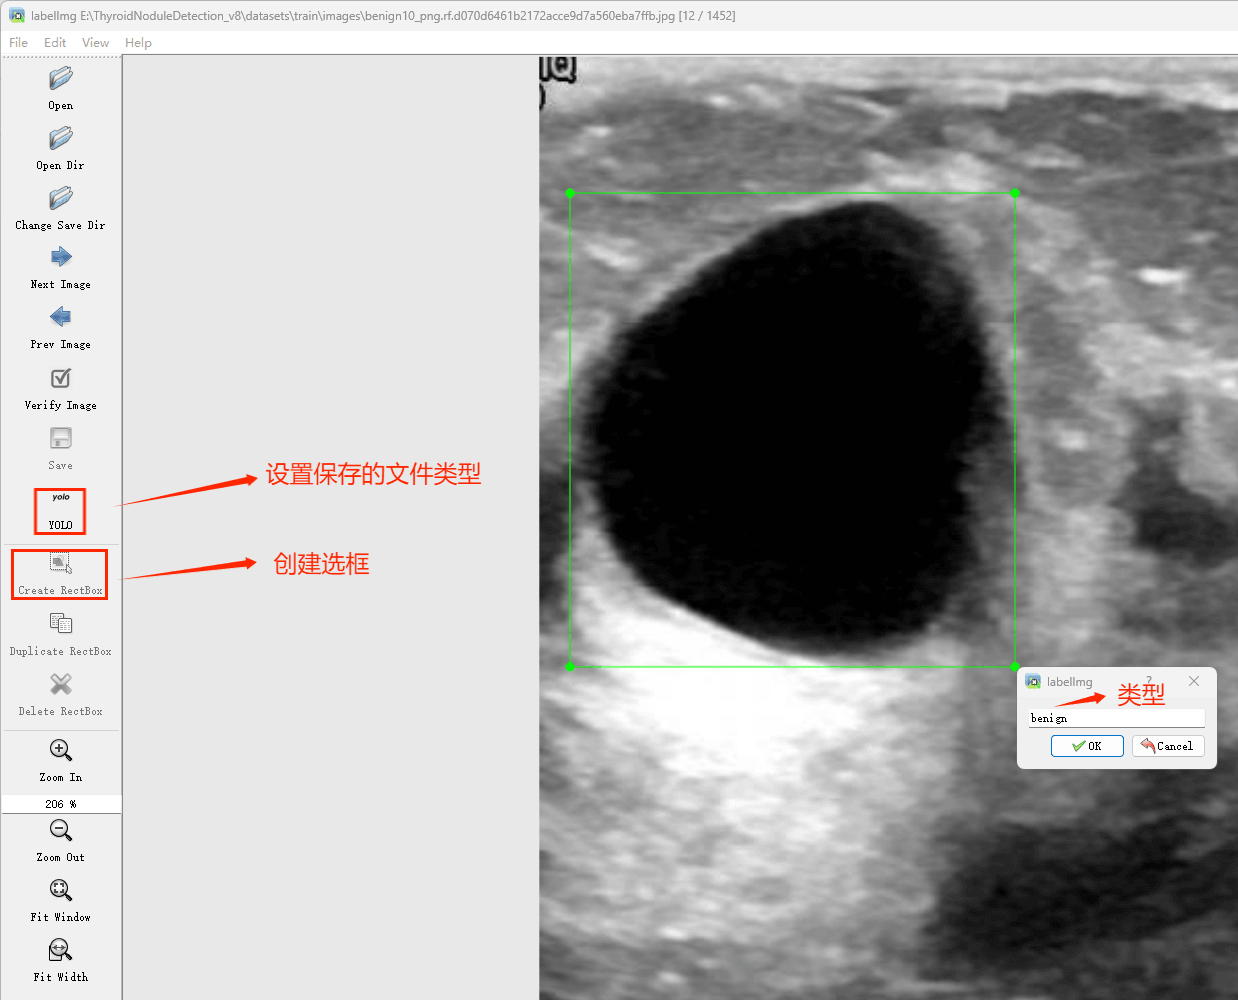

接下来就开始标注,画框,标记目标的label,然后d切换到下一张继续标注,不断重复重复。

(4)YOLO模式创建标签的样式

存放标签信息的文件的文件名为与图片名相同,内容由N行5列数据组成。

每一行代表标注的一个目标,通常包括五个数据,从左到右依次为:类别id、x_center、y_center、width、height。

其中:

–x类别id代表标注目标的类别;

–x_center和y_center代表标注框的相对中心坐标;

–xwidth和height代表标注框的相对宽和高。

注意:这里的中心点坐标、宽和高都是相对数据!!!

存放标签类别的文件的文件名为classes.txt (固定不变),用于存放创建的标签类别。

完成后可进行后续的yolo训练方面的操作。